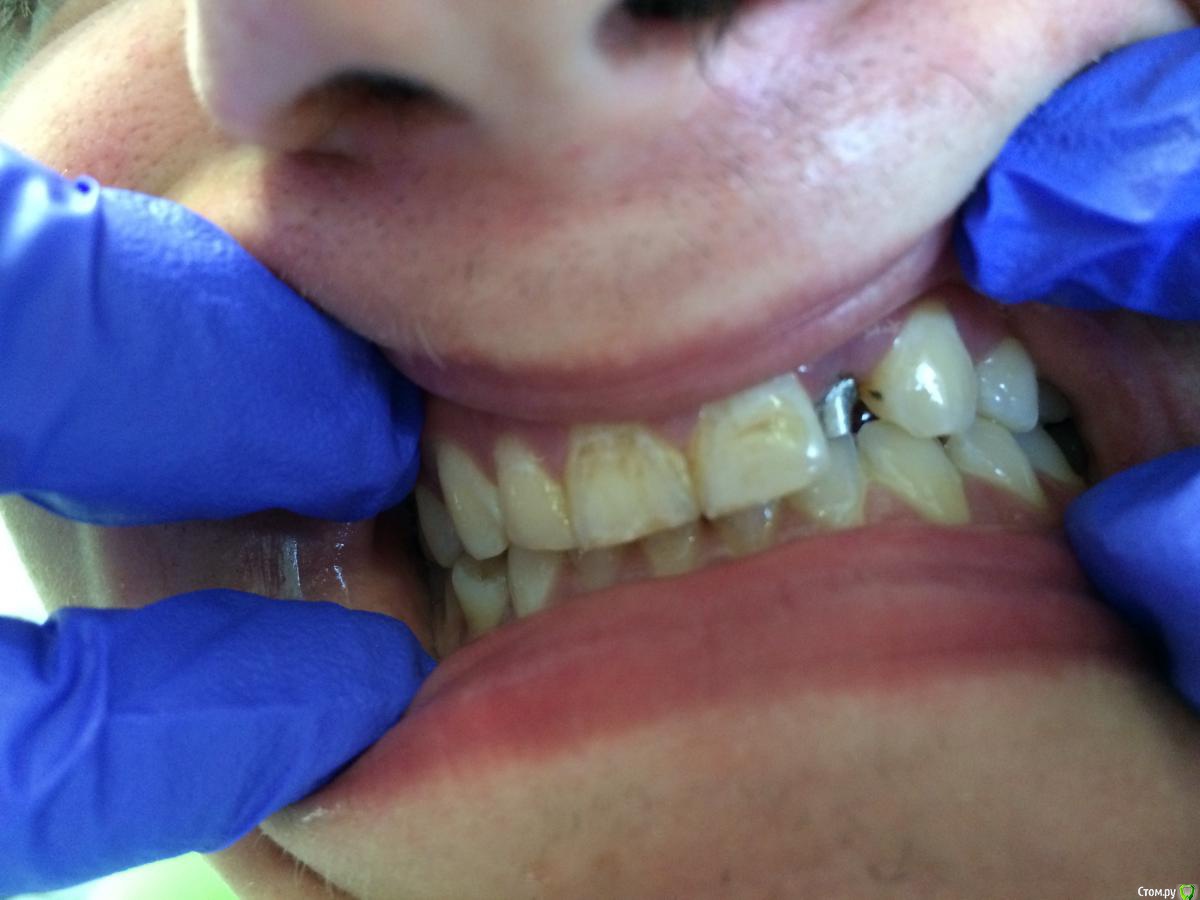

Girl Опубликовано 5 августа, 2016 Поделиться Опубликовано 5 августа, 2016 (изменено) ЗДравствуйте,коллеги. Помогите советом.Вчера ко мне обратился молодой человек 20 лет. Снял брекеты 2 года назад. Жалобы -не держится коронка на 22 На данном зубе - культевая вкладка. Прикус снижен. Места совсем нет . 26 - не анатомич формы, отсутствует щечная стенка с буграми (скошенная пломба).Как приподнять прикус? Только коронками? Что вы посоветуете?Фото плохого качества. Но что могла, сделала. Изменено 5 августа, 2016 пользователем Girl Ссылка на комментарий

BugDan Опубликовано 5 августа, 2016 Поделиться Опубликовано 5 августа, 2016 ЗДравствуйте,коллеги. Помогите советом.Вчера ко мне обратился молодой человек 20 лет. Снял брекеты 2 года назад. Жалобы -не держится коронка на 22 На данном зубе - культевая вкладка. Прикус снижен. Места совсем нет . 26 - не анатомич формы, отсутствует щечная стенка с буграми (скошенная пломба).Как приподнять прикус? Только коронками? Что вы посоветуете?Фото плохого качества. Но что могла, сделала. По этим фото можно лишь преддположить... Похоже 22 под удаление и немедленную имплантацию. Желательно винтовую фиксацию. Моляр совсем не видно. Ссылка на комментарий

StomV Опубликовано 6 августа, 2016 Поделиться Опубликовано 6 августа, 2016 ЗДравствуйте,коллеги. Помогите советом.Вчера ко мне обратился молодой человек 20 лет. Снял брекеты 2 года назад. Жалобы -не держится коронка на 22 На данном зубе - культевая вкладка. Прикус снижен. Места совсем нет . 26 - не анатомич формы, отсутствует щечная стенка с буграми (скошенная пломба).Как приподнять прикус? Только коронками? Что вы посоветуете?Фото плохого качества. Но что могла, сделала. А мне кадетс,что у зуба чрезмерная конусность и плюс короткая культя,оттого и не держится коронка,посмотрите зенит двоек,м.б. удастся сделать удлинение и норм запротезировать. Ссылка на комментарий